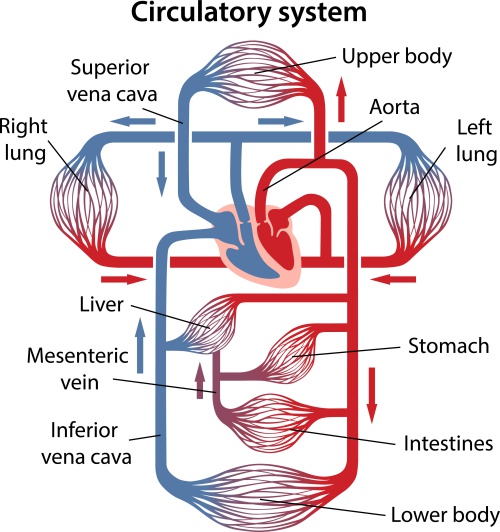

37,900+ การไหลเวียนของเลือด ภาพถ่ายสต็อก รูปภาพ และภาพปลอดค่าลิขสิทธิ์ … หัวใจกับการไหลเวียนของเลือด – ระบบไหลเวียนโลหิต

หัวใจกับการไหลเวียนของเลือด – ระบบไหลเวียนโลหิต ม.2 ระบบหมุนเวียนเลือด | Science – Quizizz

ม.2 ระบบหมุนเวียนเลือด | Science – Quizizz ระบบไหลเวียนเลือด: หัวใจ

ระบบไหลเวียนโลหิตขนาดเล็กและใหญ่: วงจร วงกลมขนาดเล็กและขนาดใหญ่ของสิทธิ … สภาติวเตอร์ By TS Council

แผนภาพแสดงการไหลเวียนของเลือดของหัวใจมนุษย์ ภาพประกอบสต็อก – ดาวน์โหลด … ระบบหัวใจและหลอดเลือด ระบบไหลเวียนโลหิต ภาพประกอบ ภาพสต็อก รูปภาพ และ …